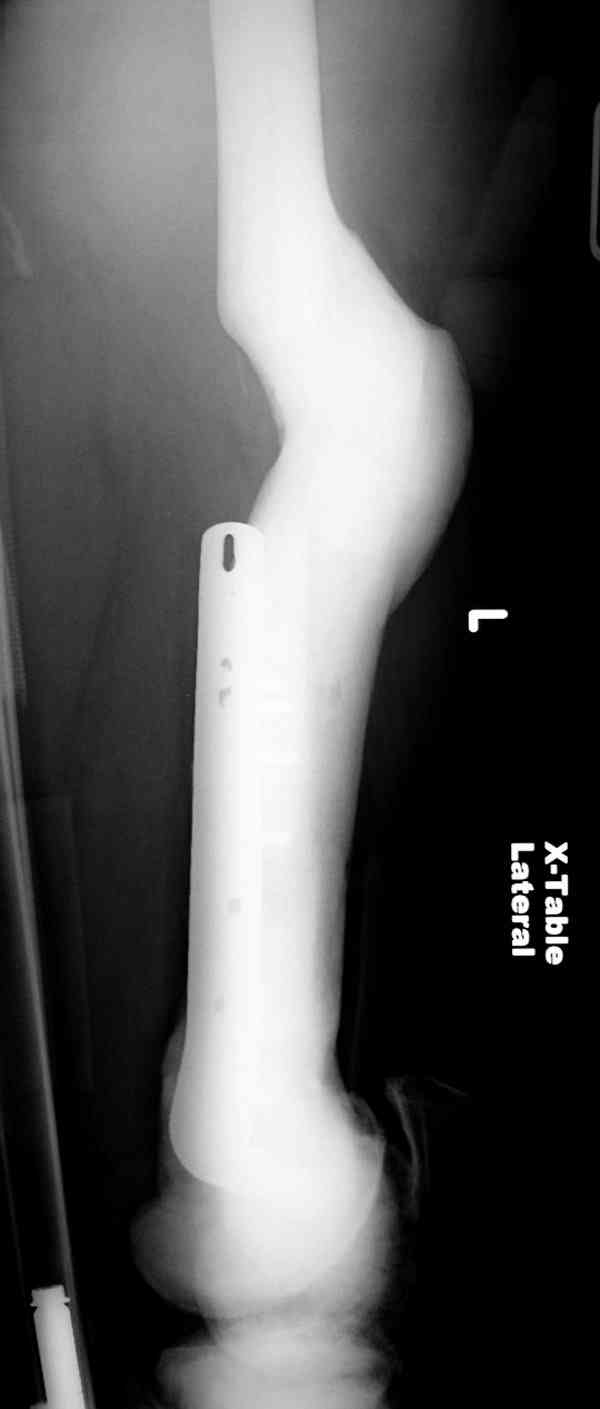

Здесь у меня дополнительные снимки с большим разрешением и в разных режимах, а то те дигитал снимки совсем очень блеклые, может, эти изображени изменят выбор тактики

Не вызывает ли подозрение, что отсутствует медуллярный канал, как просверлить канал?

Канал, возможно, действительно запаян. Но разве большие проблемы его создать и рассверлить (если только это мраморная болезн?) Уверен, в вашей клинике есть для этого всё.

1. Верхушку б\вертела всктыть спицей и рассверлить каннюлированным инструментом (14 мм).

2. Если в диафизарной части канал запаян, то, используя сам штифт, введенный в проксимальный отломок, как центратор, по нему завести спицу в центр дистального отломка и сформировать канал, сначала тонкий 4 мм.

3. Гибкими (неканнюлированными) развертками диаметром 6,7 и 8 мм последовательно расширить канал.

4. Рассверливать каннюлироваными развертками по направляющей спице до нужного диаметра.